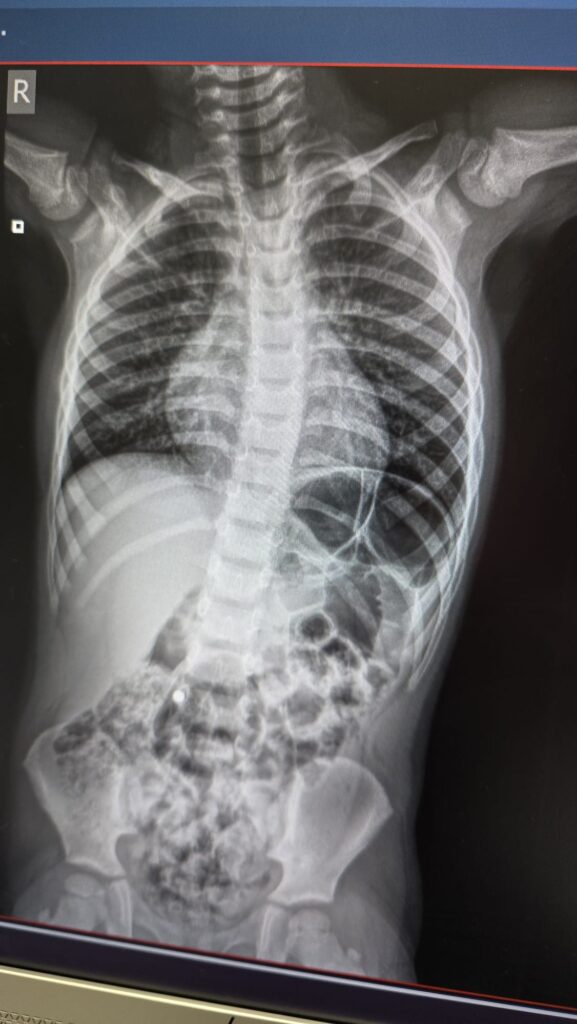

Meeri-Mall (tavainimese kommentaar): Meie käisime 1 magnetpalli tõttu EMOs ja ütlen omalt poolt, et laste sõnu sellises olukorras 100% usaldada ei maksa, et mitu ta neid täpselt neelas või ei neelanud. Kiirabi hindab ka olukorra sellisel puhul ohtlikuks ning meid võeti kohe kaasa, tehti pilt ja õnneks oli üks ja saime koju. Panen kohe illustratsiooni ka kenasti siia. Oleks neid palle olnud kaks või enam, oleks asi juba väga palju jamam olnud.